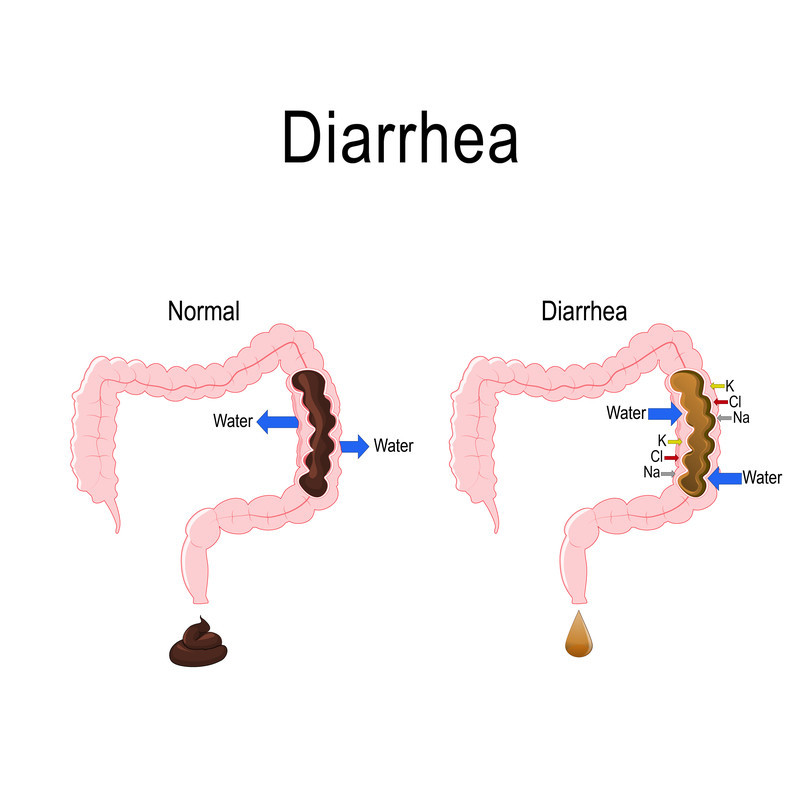

Dehydration is the most immediate risk. You lose large amounts of water and electrolytes — sodium, potassium, and magnesium — with every loose stool. Electrolyte imbalances can affect your heart, kidneys, lungs, and brain.